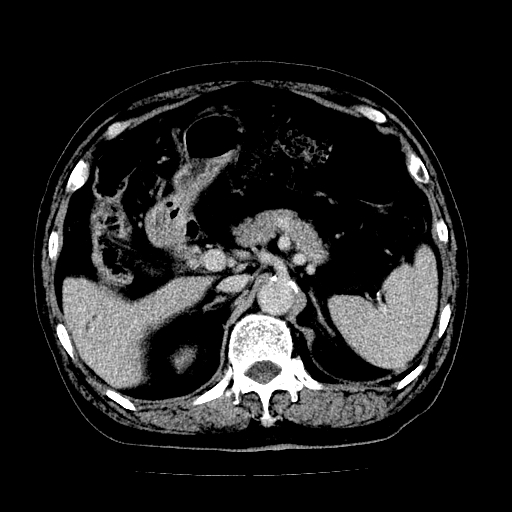

男,71岁,皮肤黄染四天。

肝内外胆管及胆总管上段扩张,考虑为梗阻所致,建议mrcp检查。

考虑胆总管癌并肝内外胆管扩张。

胰腺上端胆总管内见软组织影,强化不明显,结合临床,还是考虑低位梗阻性黄疸,胆总管癌可能性大